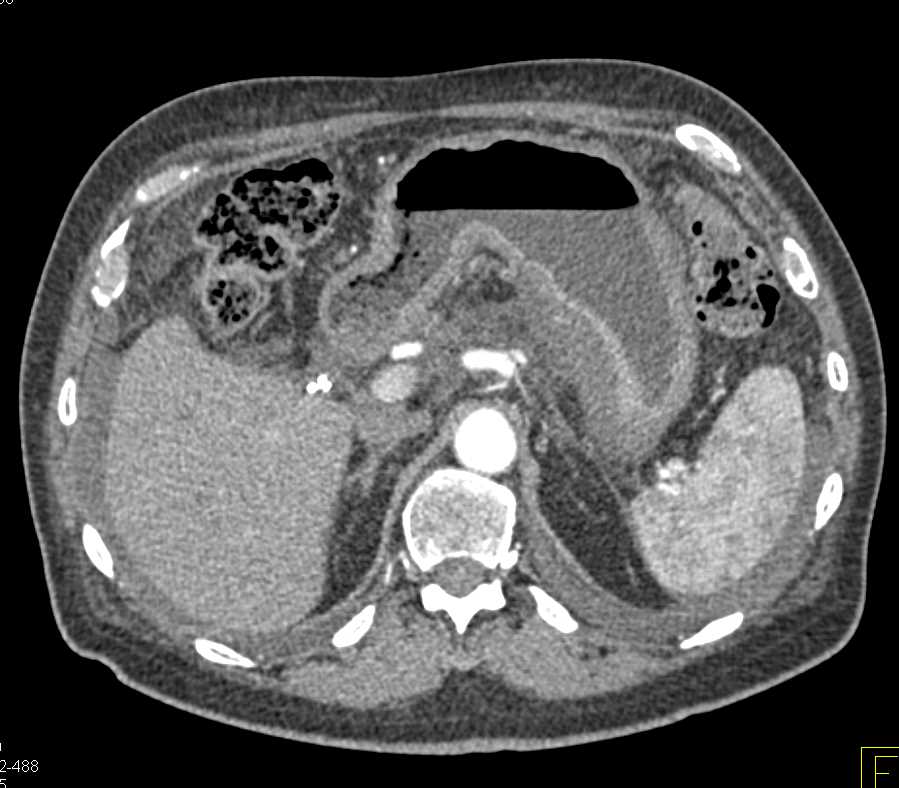

Gastric Cancer with Carcinomatosis